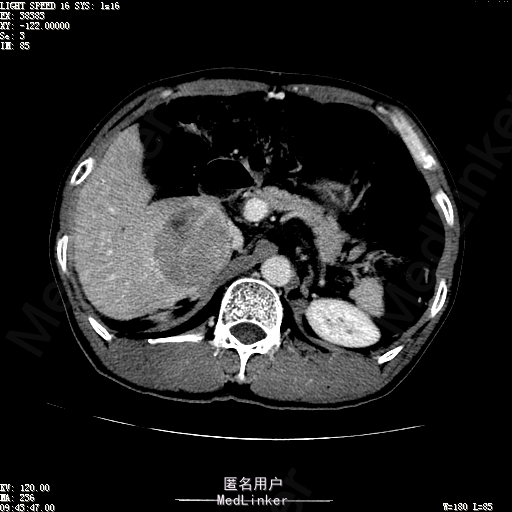

查体:体温36.4℃,脉搏76次/分,呼吸18次/分,血压110/70mmHg。神志清晰,发育正常,营养中等,体位自如,表情安静,慢性病容,检查合作。皮肤粘膜颜色正常,无瘀点、紫癜,有肝掌,无蜘蛛痣,无水肿,毛发的生长与分布正常。浅表淋巴结浅表淋巴结未触及肿大。无巩膜黄染,结膜正常。口唇红润,粘膜正常,舌正常,牙龈正常,扁桃体无肿大,无咽部充血。颈部外形对称,颈静脉正常,肝颈静脉回流征阴性,气管居中。甲状腺正常,无颈部血管杂音。胸部形态正常,呼吸运动平稳规律,无呼吸困难,肋间隙正常。触诊语颤正常,无胸膜摩擦感,肺下界位于右锁骨中线第六肋间。呼吸音正常,未闻及干湿啰音,无胸膜摩擦音。无心前区隆起,心尖搏动正常,心率:76次/分,心律齐,心音正常,无杂音,无心包摩擦音。无大动脉及周围血管征,无奇脉及交替脉,无水冲脉,无枪击音,腹型对称,无腹壁静脉曲张,未见胃肠型及蠕动波,无瘢痕,脐部正常。无压痛,无反跳痛,无腹肌紧张,无腹部包块。肝未触及,Murphy征阴性,脾未触及,肾未触及,无移动性浊音。无肝区叩击痛,无肾区叩击痛,无脾区叩击痛。肠鸣音正常4次/分,无气过水声。外阴及肛门:未查。四肢正常,关节正常,无下肢水肿,无下肢静脉曲张,无杵状指趾。 辅助检查:彩超:肝表面欠光滑,肝内占位5.2*5厘米 ct如下图

诊断:乙肝肝硬化 代偿期 原发性肝癌。 患者病史明确,目前化验转氨酶轻度升高,说明有活动性肝损伤,白蛋白降低提示肝脏合成代谢功能下降,AFP从一年前至今逐渐升高,提示活性肿瘤细胞增多。CT所见明确诊断肝癌,并有周围卫星灶,应近期行TACE治疗。 处置:DSA下肝动脉造影及TACE 手术简要经过:患者平卧位,术区皮肤消毒,铺手术巾,2%利多卡因局麻后,Seldinger法穿刺右股动脉,入血管鞘,5F猪尾管腹主动脉造影,超滑导丝yidao5F RH管腹腔干、肠系膜上动脉、左肾动脉分别造影,腹腔干造影时,见肝右叶7-8处小结节样肿瘤染色,未见外凸生长较大病灶染色。微导管超选肝右动脉注入三氧化二砷碘油混悬液10毫升,横结肠遮挡部位见较大病灶有伞状碘油沉积。复查造影未在见肿瘤染色,拔出导管和血管鞘,穿刺处压迫止血,加压包扎。术毕。

患者术后8天来,无不适,无发热,无腹痛和腹胀,无恶心呕吐,食欲睡眠好,尿便正常。 查体:神志清,巩膜无黄染,心肺听诊无异常,腹软,无压痛,肝脾肋下未触及,移动性浊音阴性,双下肢无浮肿。 复查化验结果:丙氨酸氨基转移酶 116 U/L、天门冬氨酸氨基转移酶 41 U/L、胆碱酯酶 1995 U/L↓、总蛋白 56.3 g/L、白蛋白 25.9 g/L。白细胞计数 5.8 10^9/L、红细胞计数 3.18 10^12/L、血小板计数 175.0 10^9/L、*血红蛋白 83 g/L、血小板分布宽度 15.7 、血小板压积 0.175 %、*红细胞压积 24.6 %、平均红细胞血红蛋白 26.1 pg、平均红细胞血红蛋白浓度 337.0 g/L、平均红细胞体积 77.5 fL、平均血小板体积 10.0 fL、嗜碱性粒细胞百分比 0.4 %、嗜碱性粒细胞数量 0.02 10^9/L、中性粒细胞百分比 70.4 %、中性粒细胞数量 4.10 10^9/L、嗜酸性粒细百分比 2.1 %、嗜酸性粒细胞数量 0.12 10^9/L、单核细胞百分比 12.2 %、单核细胞计数 0.7 10^9/L、淋巴细胞数量百分比 14.9 %、淋巴细胞计数 0.9 10^9/L。甲胎蛋白 23564.00 ng/mL 患者术后第8天开始行FOLFOX6化疗。CT上可见明显碘油沉积,术后甲胎蛋白下降治疗有效。嘱患者术后必须定期复查